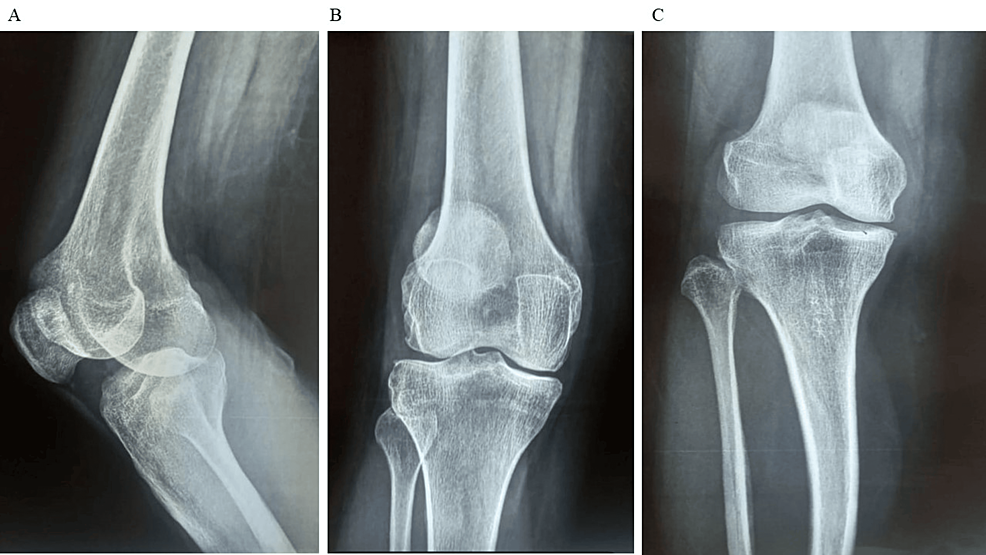

平均WOMAC評分從基線時的56.8±11.5下降到六個月時的41.2±10.6。此外,還監(jiān)測了不良事件的發(fā)生情況,報告了七起不良事件,占參與者的28.0%。這些發(fā)現(xiàn)強調(diào)了該治療在六個月內(nèi)減輕疼痛和改善功能結果方面的有效性。下圖2顯示了開始干細胞治療后骨骼的側(cè)視圖和前后視圖。?

圖2:顯示了開始干細胞治療后骨骼的側(cè)視圖和前后視圖

圖2:A:干細胞治療后(側(cè)視圖),B:干細胞治療后前后位 (AP) 視圖,C:干細胞治療后前后位 (AP) 視圖。